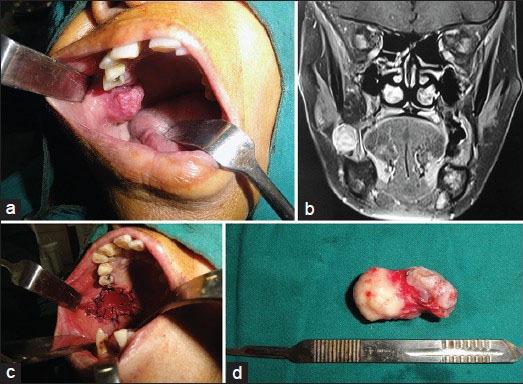

Myoepithelial carcinoma is a rare neoplasm of salivary glands that account for < 1% of all salivary gland tumors. The most common sites of involvement are major salivary glands mainly parotid gland. Intraorally, it can arise from minor salivary glands; palate is the most common site of occurrence. It also occurs in nasopharynx, paranasal sinuses, nasal cavity and larynx in head and neck region. Myoepithelial tumors were first described in 1943. Their malignant variant, myoepithelial carcinoma, was first reported by Stromeyer et al., in 1975, characterized by distinct morphologic heterogeneity and an infiltrative growth pattern into adjacent tissues. Here, we report a rare case of a 55-year-old female with myoepithelial carcinoma of buccal mucosa. It was also rare because of unusual location of tumor. Our patient was treated with wide local resection and remained free of disease for 15 months.

肌上皮癌是一种罕见的唾液腺肿瘤,占所有唾液腺肿瘤的比例不到1%。最常受累的部位是主要的唾液腺,主要是腮腺。在口腔内,它可起源于小唾液腺;腭部是最常见的发生部位。它也发生于头颈部区域的鼻咽、鼻窦、鼻腔和喉部。肌上皮肿瘤于1943年首次被描述。其恶性变体——肌上皮癌,于1975年由斯特罗迈尔等人首次报道,其特征是形态学上具有明显的异质性以及向相邻组织浸润性生长的模式。在此,我们报告一例罕见的55岁女性颊黏膜肌上皮癌病例。该病例还因肿瘤位置不寻常而罕见。我们的患者接受了广泛局部切除治疗,并且在15个月内无疾病复发。